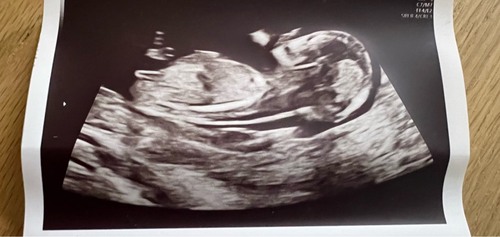

Gisteren op basis van de 13 weken echo werd een meisje gezegd, nu hebben we de geslachtsecho gehad en kon ze deze nub zien maar de doen geen uitspraak omdat ze niet tussen de beentjes konden kijken 🥲 maar dit is toch ook een meisjes nub?

Dit vind ik wel een meisje ja. Heb je er nog eentje meegekregen?

Niet eentje waar de nub zichtbaar is denk ik, baby zit graag op de billetjes dus ze kunnen geen potty shot nemen en ze zei alleen: voor nu mag je zelf een conclusie trekken op basis van je nub, maar ik mag niets zeggen 😂

Juist omdat je baby graag op de billetjes zit is de nub dus niet heel erg goed te beoordelen. Op deze foto denk ik weer 💙 Je ziet, ik ga heen en weer😂 Dit waren ze allemaal?